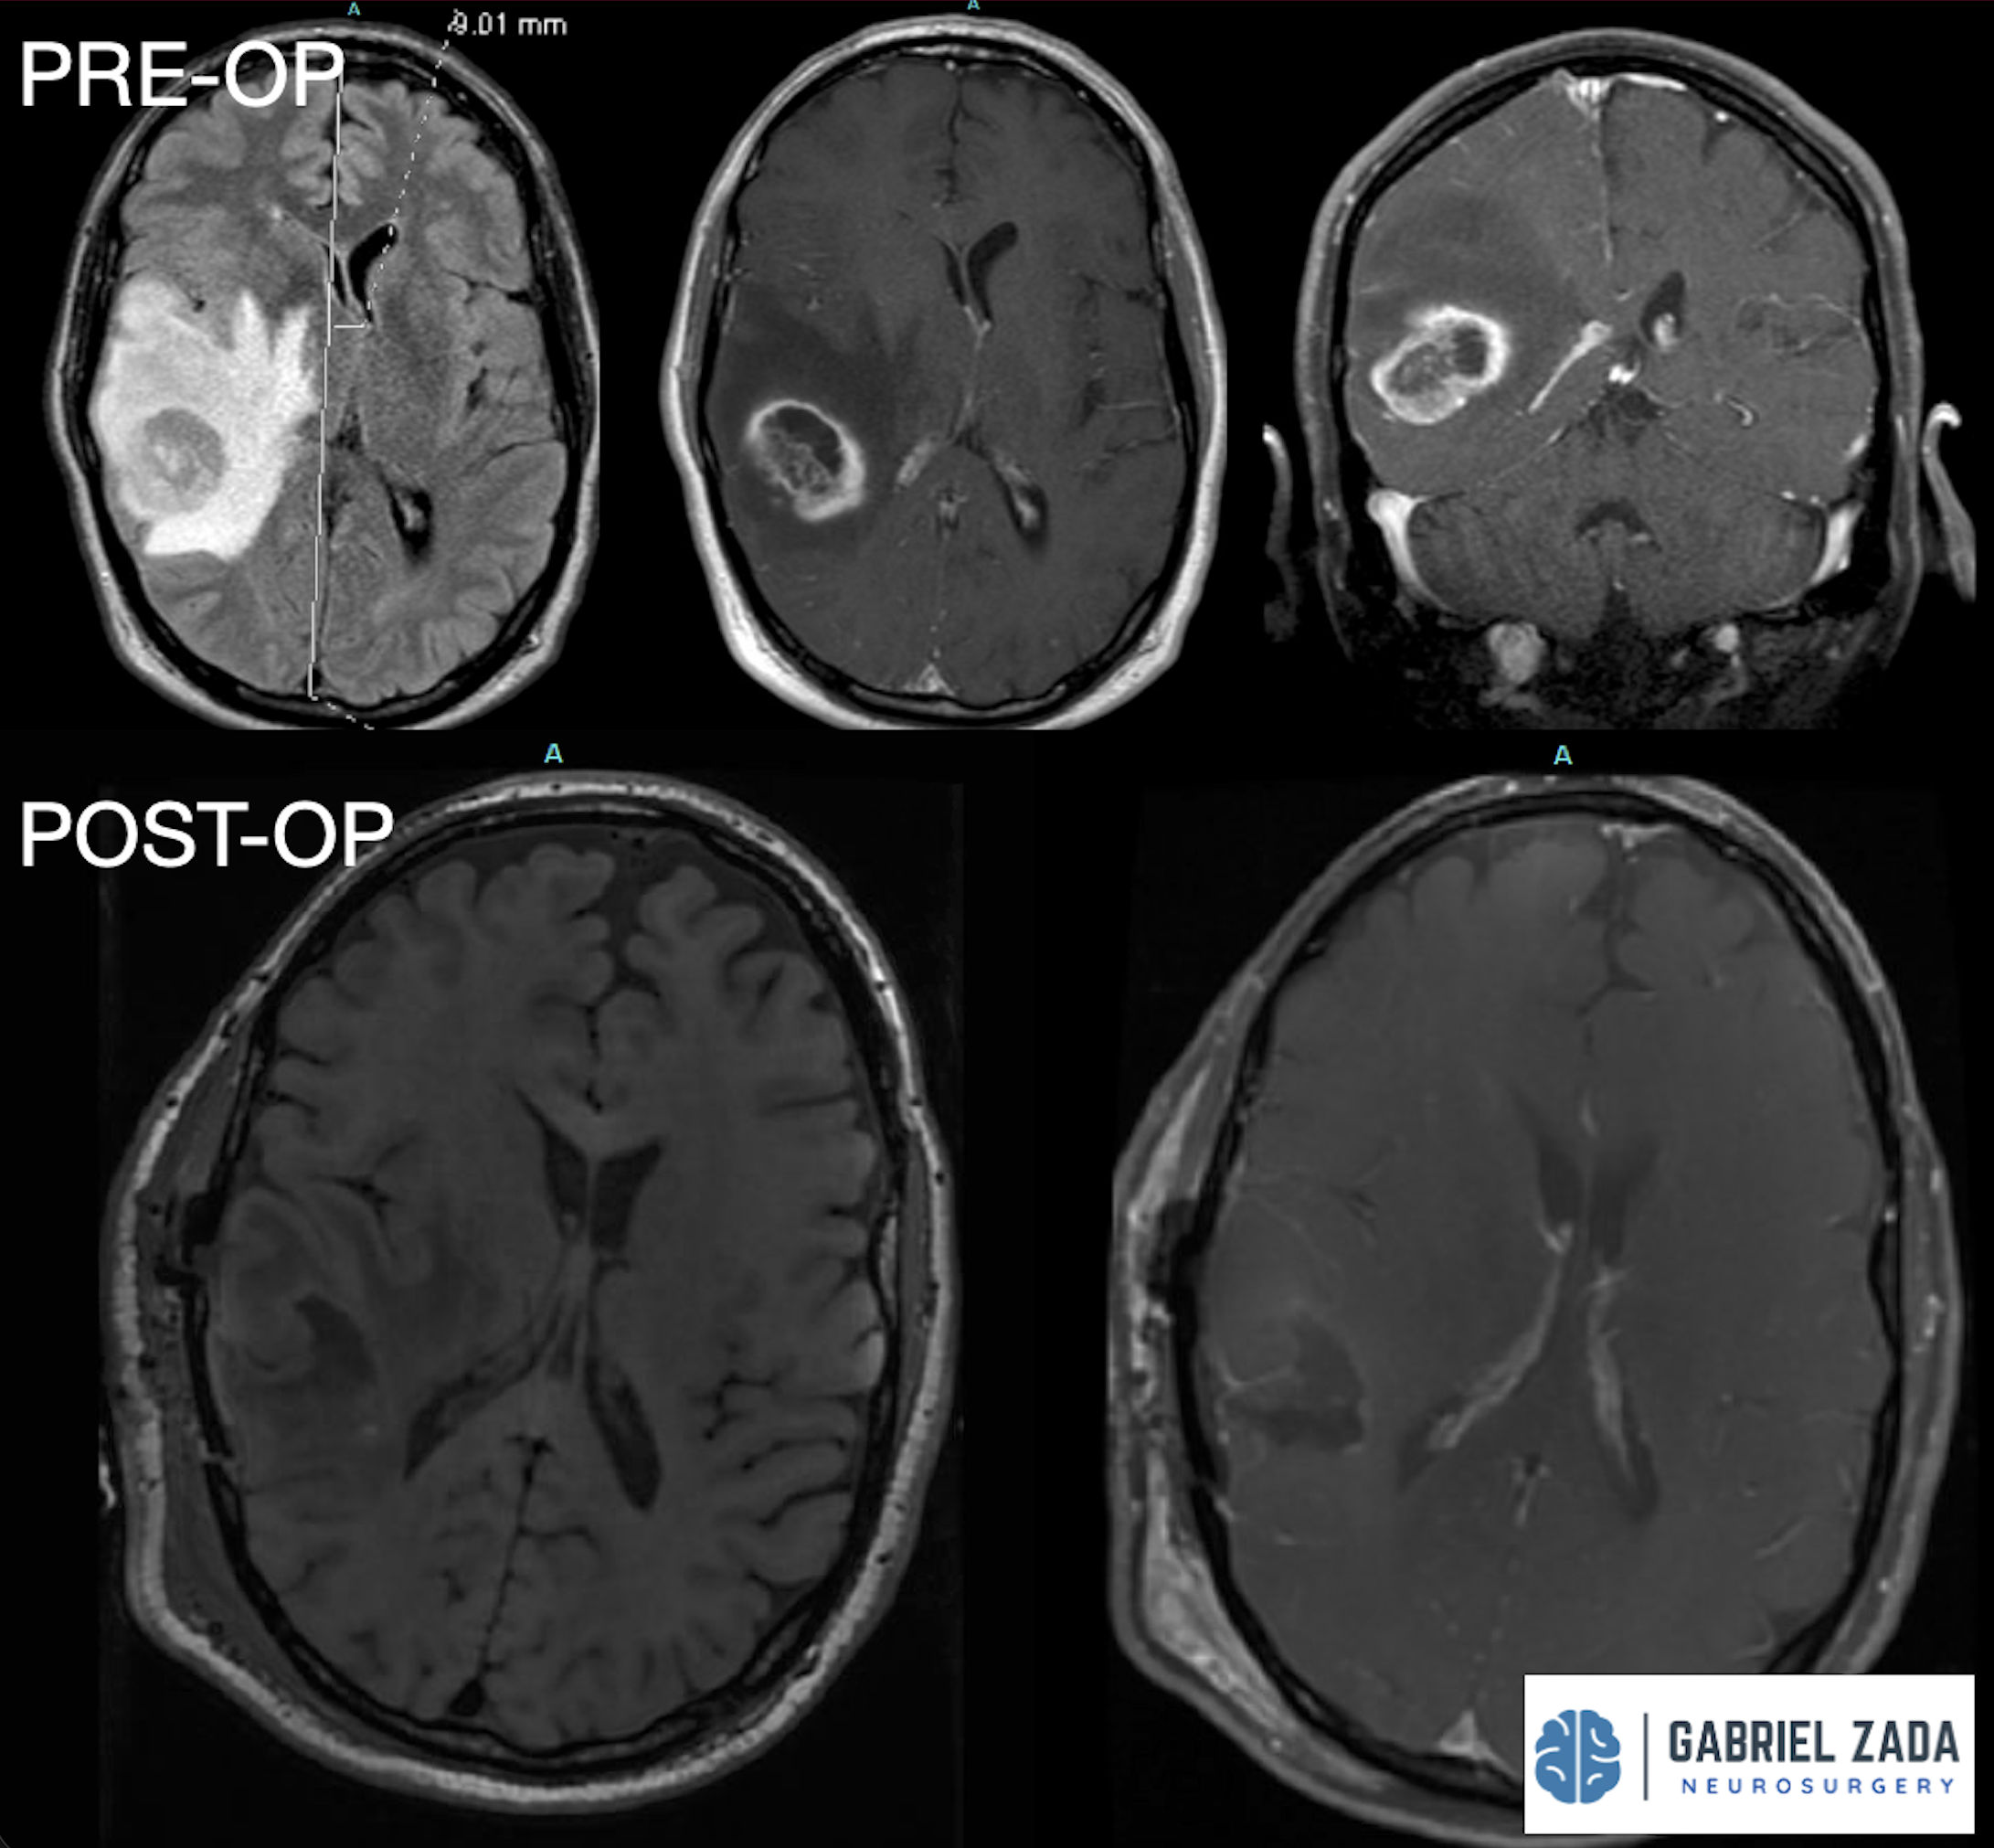

Explore this comprehensive gallery featuring pre‑ and post‑operative imaging of patients with skull‑base tumors treated by Gabriel Zada, MD, MS, FAANS, FACS. These cases highlight Dr. Zada’s expertise in advanced neurosurgical techniques and outcomes.

*Representative cases shown for educational purposes. All images de-identified. Individual results vary.